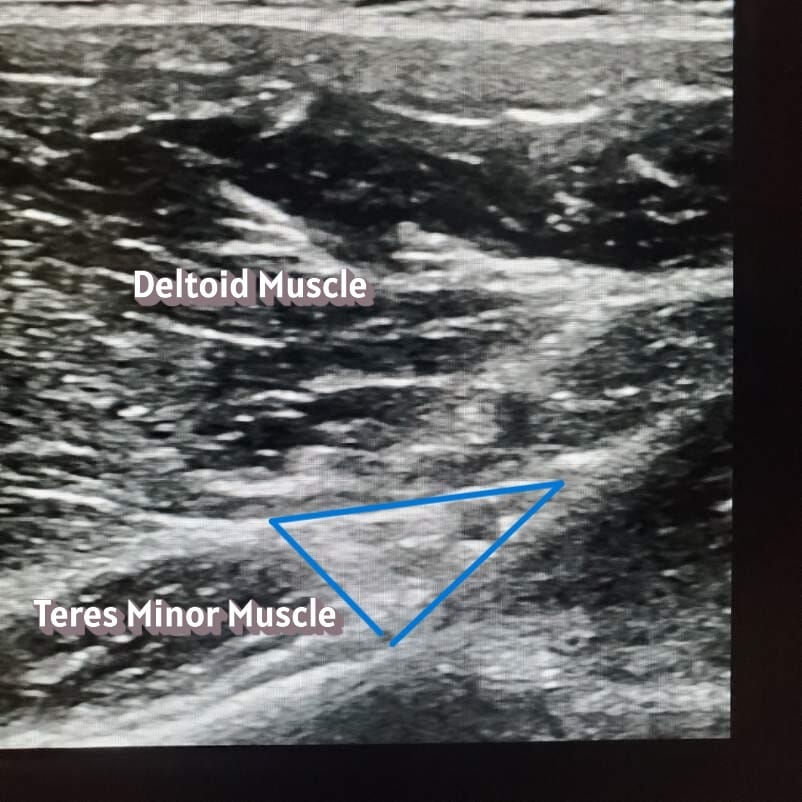

Then, there’s the anatomy behind the selective axillary nerve block. The term “selective” is used here to distinguish this block from the axillary brachial plexus block. The axillary nerve branches off the posterior cord of the brachial plexus, travels through the axilla, and then wraps around the humeral neck and continues to innervate the deltoid muscle, teres minor muscle, and superolateral cutaneous aspects of the shoulder.4

Now on to the selective axillary nerve block. Keep patients in the same sitting position, but now have them let go of the contralateral shoulder and relax their arm by their side. Place the probe in the sagittal position on the posterolateral side of the humeral head. After locating the head of the humerus, scan caudad to the transition between the humeral metaphysis and diaphysis. As the straight line of diaphysis now curves into the metaphysis, put the color setting on the ultrasound machine and identify the posterior circumflex humeral artery and the small axillary nerve running in the fascial compartment between teres minor and the deltoid muscles.11 Just like in the approach to the suprascapular nerve, a nerve stimulator can help to identify an axillary nerve that is difficult to visualize on ultrasound. Look for a deltoid and/or teres minor twitch if using a nerve stimulator. Place 10 ml of local anesthetic into or deep to the fascial compartment containing the axillary nerve and the posterior circumflex humeral artery. The nerve is not always visible, so identifying the bony, muscle, fascial, and arterial landmarks is important. Injecting into or deep into the fascial compartment containing the nerve is sufficient to block this nerve. The injection doesn’t need to be immediately adjacent to the nerve. If the nerve isn’t visualized, it’s advisable to inject deep into the fascial compartment where the shaft of the humerus transitions to the head of the humerus to avoid nerve injury.